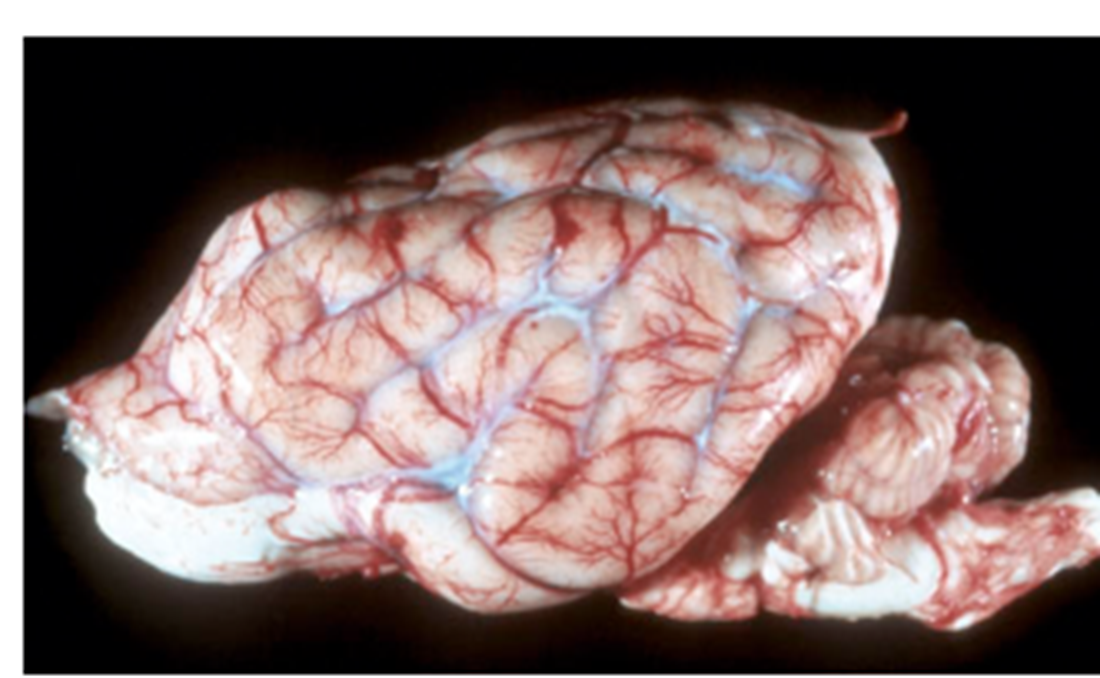

What pathology is shown in this image?

Polioencephalomalacia (image)

What pathology is described as having a yellow discoloration and softening of the cerebrocortical grey matter and is autofluorescent under UV?

Polioencephalomalacia (description)